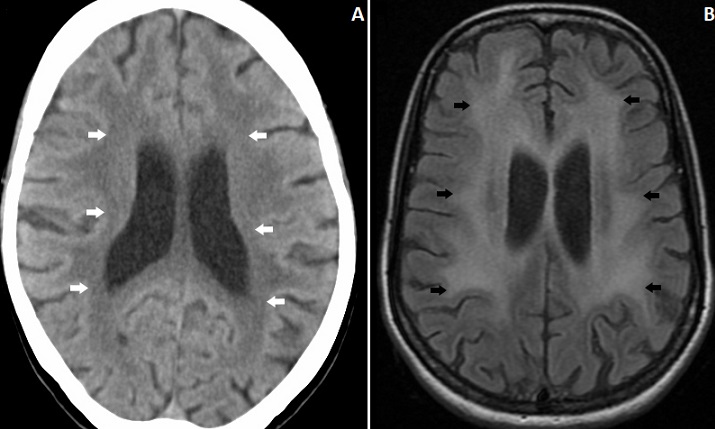

A 40-year-old female presented with progressive memory loss over the past 1-month. She had one episode of generalized tonic clonic seizure 2-months back, but did not take any treatment. She had significant involuntary weight loss. On examination she was emaciated and had a BMI of 16.4. Neurological examination showedcognitive decline in the form of loss of recent memory,judgment and abstract thinking, with preserved language and visuospatial orientation. There were no focal neurological deficits. She was tested positive for HIV. Her CD4+ count was 21/µL. Computed tomographyof the brain revealed bilateral hypodensities in the periventricular area (A). MRI of the brain showed bilateral symmetrical periventricular white matter FLAIR hyperintensities in frontal and parietal lobes with diffuse brain atrophy suggestive of HIV encephalopathy (B). She was started on combination antiretroviral therapy with tenofovir, lamivudine and efavirenz and discharged. HIV encephalopathy refers to neurocognitive disorders associated with HIV infection. It usually occurs in late stages of HIV-infection and correlates with advanced immunosuppression. Earliest recognizable findings include impairment of attention and concentration. This progresses to frank dementia, personality changes and motor abnormalities. Neuroimaging typically shows global cerebral atrophy with symmetrical white matter hyperintensities predominantly in the periventricular area. Lesions of progressive multifocal leukoencephalopathy can mimic HIV encephalopathy, but are usually asymmetric, involve the peripheral “U” fibres first and have predilection for parieto-occipital lobes.Treatment of HIV encephalopathy is initiation or intensification of anti-retroviral therapy, and psychomotor improvement is usually seen after therapy.